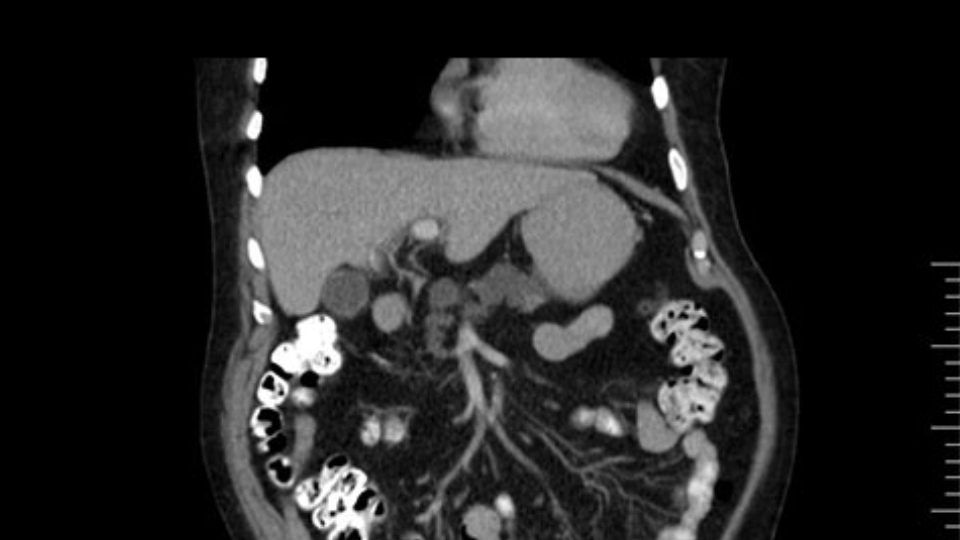

The other thing I look at is the gastroepeiploic arcade- which is this thing here- which is where the gastroepeiploic vein joins the portal vein. I call it the gateway to the neck of the pancreas because you pretty much have to divide it to get to the neck. The middle colic vein usually drains either into it or nearby. I think we’re seeing it here. Again,that can be divided and I usually divide those two and it helps me get under the neck. Again, there’s no issues here with the tumor so it’s nice from that perspective. If I was concerned about the vein, which I’m not here, I would go to the coronal view. It’s a nice way to look at the vein on just a couple of cuts and you can see a beautiful view of it here. There’s the portal vein, there’s the head of the pancreas. There’s the tumor. It’s a little closer here than it looks on the other one. I doubt it’s involved. If it’s touching, it may not be invading it but even if it was, it's a short segment. Anyways, there’s the SMV there’s the splenic vein, and everything looks good. You can see the stent. I ignore the stent. It’s the most dramatic looking thing in the picture but it’s actually the least important.

Then you look for anomalies. The one you worry about the most doing a Whipple is a replaced or aberrant right hepatic artery coming off the SMA at its origin. So again, find the SMA. You can find it because the renal vein goes through it. Follow it up, up-up-up. Nothing coming off of there that I can see here. Nothing coming off of it, nothing coming off of it and just to confirm it, look at the celiac trfurcation. There’s the celiac, there’s the bifurcation, there's the splenic artery, hepatic artery. Make sure there’s a right, which there is here. The right usually goes under the bile duct: important when you’re going around the bile duct to do a Whipple. A replaced right goes under the portal vein and the bile duct way over here on the right. That’s about it.